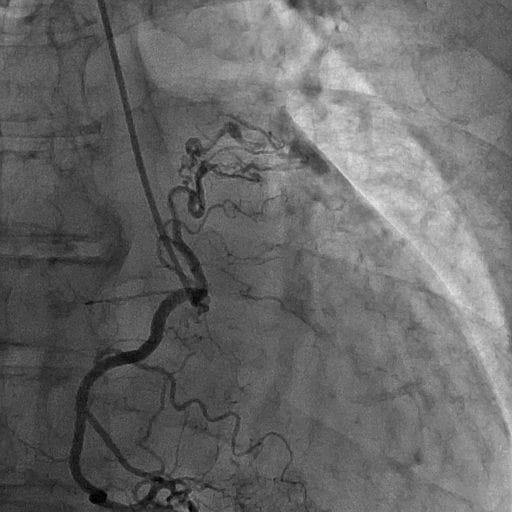

図5.冠動脈造影(右冠動脈)AP拡張期

右冠動脈造影にて右冠動脈肺動脈瘻を認める。

図6.冠動脈造影(右冠動脈)AP収縮期